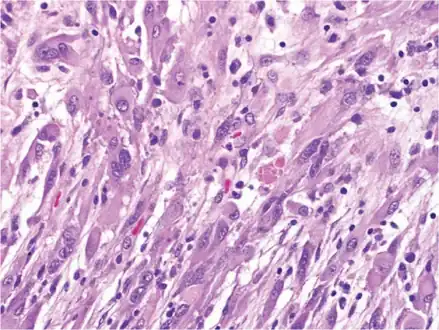

Pleomorphic xanthoastrocytoma (WHO grade II); Pleomorphic xanthoastrocytoma represents a distinctive glioma subtype

Pleomorphic xanthoastrocytoma, as visualized under a microscope